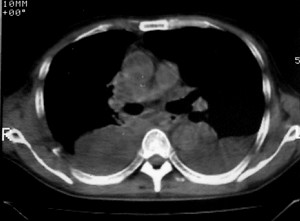

m ,60岁,右上肺ca术后一月。

右侧肺癌术后:肝内可见多个大小不等的低密度结节影。腹腔及双侧胸腔大量积液。考虑:肺癌并胸膜及肝脏转移。

纵隔淋巴结增大,双侧胸水。考虑术后残留,而非复发。

腹水,肝及右肾多发低密度影。考虑转移。

肝及右肾转移瘤,双侧胸水

右肾及肝内多发转移瘤,胸水。

肺癌术后 。双侧胸水 纵隔 胸膜 肝脏转移